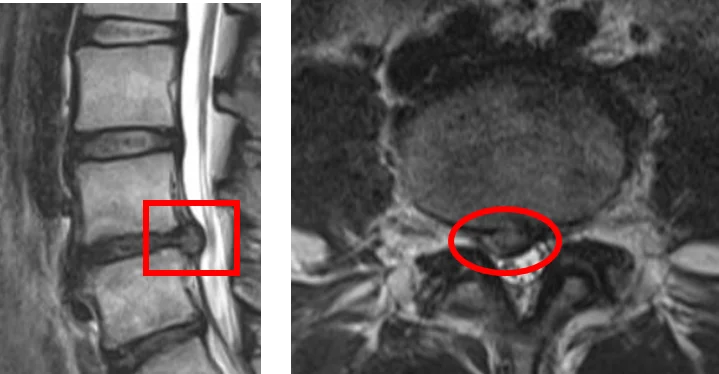

Когда фиброзное кольцо повреждается, ядро диска вытекает за его пределы. Образуется межпозвоночная грыжа.

Диагностика грыжи межпозвоночного диска включает оценку симптомов, физикальное обследование и проведение рентгенографии, МРТ или КТ.

Считается, что физикальное обследование и МРТ являются необходимыми для диагностики межпозвоночной грыжи.

По снимкам МРТ можно определить наличие/отсутствие дегенерации межпозвоночных дисков, состояние суставов, связок и нервных корешков, наличие/отсутствие воспаления. Это позволяет поставить точный диагноз.

МРТ-снимки позволяют диагностировать не только межпозвоночную грыжу, но и стеноз позвоночного канала, опухоли позвоночника, инфекции и переломы.